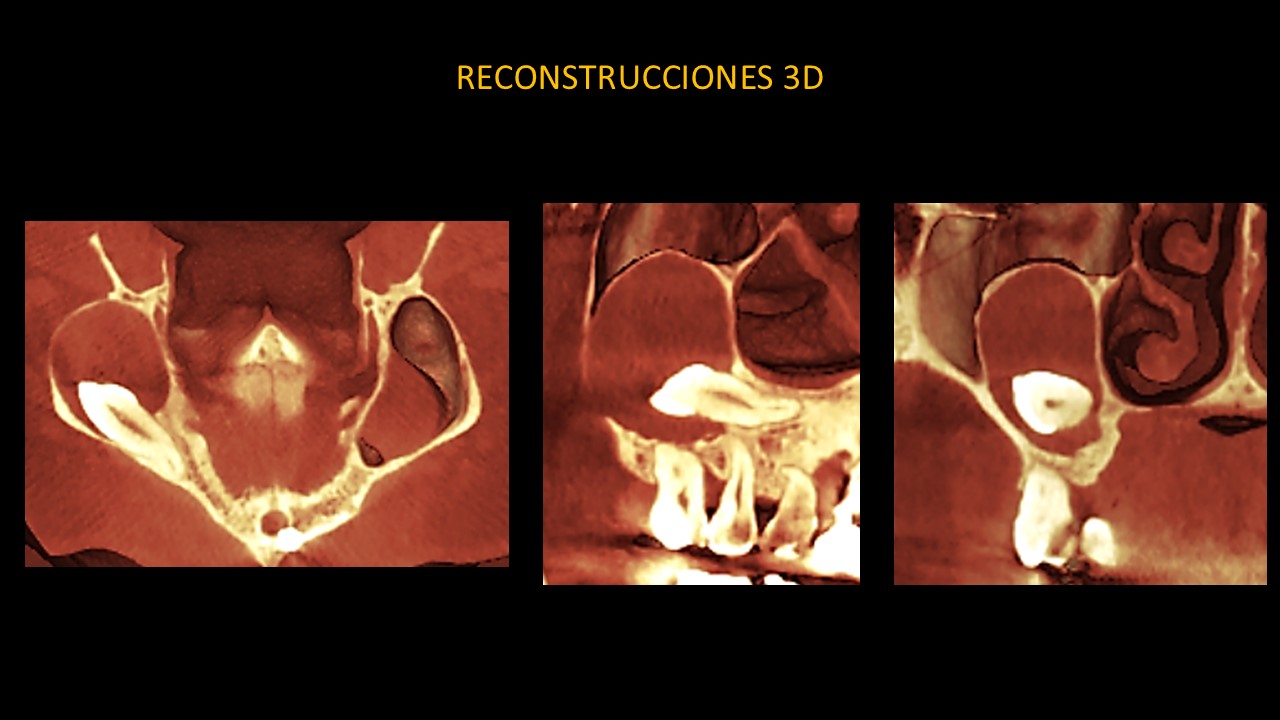

Figura 6

Las reconstrucciones tridimensionales (Figura 6) nos permiten ilustrar de manera didáctica lesión y sus características que afectan a la parte dentaria como a los reparos anatómicos adyacentes.